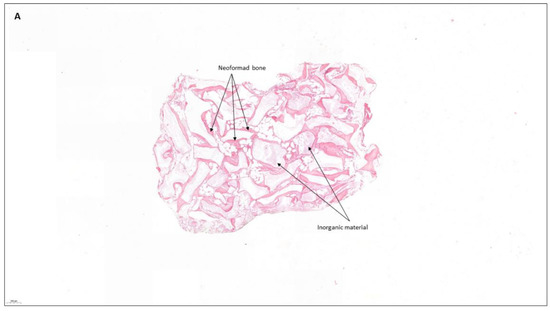

4.2. Patient No. 2

| 2 M 52 | NO [-] Alveolar ridge preservation | No [Yes] | G | No | M | Graft loss and self-limited alveolitis | No |